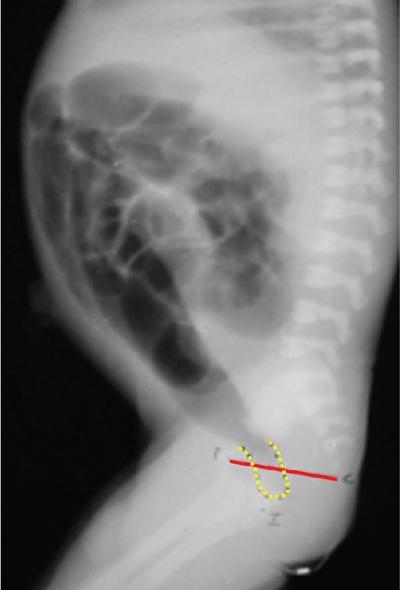

Arun Gupta, Manisha Jana, Devasenathipathy Kandasamy Anorectal malformations (ARM) are uncommon congenital malformations. They can either be found as an isolated anomaly or in association with other congenital malformations. The age of presentation and clinical presentation can have wide variation. In order to understand the complex anatomic details of the ARM, it is imperative to know the embryology and development of the normal anal canal. In the early embryonic life (4th–5th week), the primitive hindgut and the allantois communicate with each other at the cloaca. The membrane covering the cloaca at the caudal end is called cloacal membrane. During the 6th week of gestation, a sheet of mesenchyme (urorectal septum) grows between the allantois and hindgut. Eventually, lateral and midline folds develop in the cloaca, thereby dividing the common cavity into two parts: anteriorly urogenital sinus and posteriorly anorectum. Gradually, the embryo starts to lengthen and curve inwards. As a result, the distance between cloacal membrane and the tip of urorectal septum decreases and eventually, they meet each other. Consequently, the urogenital sinus and anorectum get completely separated (Fig. 7.6.1). In a later stage of gestation (7th–8th week), the anal canal gets secondarily occluded by epithelial plugs, which again gets recanalized to form the lower anal canal. Henceforth, it can be understood that any aberrations in the normal development at an earlier stage of gestation would result in a more severe degree and higher level of communication between urogenital system and anorectum. Any insult at a later stage of development will result in a low ARM, which will mostly have an abnormal anal opening in a normal position and no urogenital communication with the hindgut. Over the years, many classification systems for ARM have been introduced. Three major classifications are: Anorectal agenesis without fistula Anorectal agenesis with Rectal atresia Anorectal agenesis without fistula Anorectal agenesis with Rectal atresia H or N type fistula* Anal agenesis without fistula Anal agenesis with rectobulbar urethral fistula Anorectal stenosis Anal agenesis without fistula Anal agenesis with low rectovaginal fistula Anal agenesis with rectovestibular fistula Anorectal stenosis *Not described in original classification. #Site of anal opening is usually low but variable (1 and 2: at normal anal site; 3 and 4: at perineal site; 5–7: at vulvar location). Anorectal agenesis without fistula Anorectal agenesis with rectoprostatic urethral fistula Rectal atresia Anorectal agenesis without fistula Anorectal agenesis with rectovaginal urethral fistula Rectal atresia Anal agenesis without fistula Rectobulbar urethral fistula Anal agenesis without fistula Rectovaginal fistula Rectovestibular fistula Anal stenosis Anocutaneous fistula Anal stenosis Anocutaneous fistula Anovestibular fistula Rare Rare Anal or anorectal agenesis without fistula Rectal atresia Anal or anorectal agenesis Anal or anorectal agenesis without fistula Rectal atresia Cloacal anomalies Anal stenosis Imperforate anus without fistula Anal agenesis with rectoperineal fistula Anal stenosis Imperforate anus without fistula Anal agenesis with rectoperineal fistula Anal agenesis with rectovestibular fistula International classification was considered by some to be too detailed and too complex. However, in the authors’ experience, this system should ideally be followed in a high-volume teaching institute. A simplified version of it was, therefore, considered and is known by the name of Wingspread classification (so called because the meeting to decide it was held at the Wingspread convention centre in Racine, Wisconsin). More recently, another classification was proposed in the Krickenbeck conference on ARM in 2005. There are some common features/differentiating points in all the classification systems, namely the level of bling rectal pouch and presence/absence of fistula. Evaluation of a child with suspected ARM starts with a thorough clinical examination. Careful perineal examination should be performed to look for the number and location of the orifices. If an external anal orifice is appreciable, a low anomaly should be suspected. The location of anal orifice may be variable (Table 7.6.1). To the contrary, a flat perineum (no anal dimple or orifice) suggests a high anomaly. If there is evidence of meconium at urethral orifice/history of meconium in urine, it indicates presence of an internal fistula. In all suspected cases of high malformation, colostomy should be done, followed by detailed evaluation for the delineation of internal anatomy by contrast studies (discussed later). In the female child, if there is only one perineal opening, a cloacal malformation is likely. If two orifices are visible in the vulva with no anal orifice, then one of them is of the urethral, while the other one is of the vaginal orifice. Meconiun would come from the latter due to the associated recto-vaginal fistula. Colostomy is indicated in both the situations. If three orifices are visible, then two of them are respectively, of the urethra and the vagina, both at their normal site, while the third one is the bowel which could be at the normal anal site, or it might open as a fistulous track anteriorly at an abnormal site – either in the perineum or in the vestibule. Two most important investigations in the evaluation of ARM are invertography and contrast studies. Invertography is a procedure described back in 1930 by Wangensteen and Rice. This involved obtaining a lateral radiograph of the neonate, held upside down. An ideal time to obtain this radiograph is about 6–8 hours after birth, so as to allow the intestinal gas to reach the rectum. The thighs of the baby should be flexed, and X-ray beam should be centred at the greater trochanter. Anal dimple should be marked by barium paste. A properly done invertogram should have the following: On an invertogram, the distal part of the blind-ending bowel loop should be localized in relation to some specific bony landmarks, namely: Additional points to be evaluated on an invertogram are: presence/absence of spinal anomalies; and presence of gas in urinary bladder/vagina. Invertography is reported to be very accurate in differentiating a low-type fistula from intermediate/high type. However, the accuracy depends on how well the study has been performed. While interpreting invertogram, one must be aware of the pitfalls of this study (Table 7.6.4).

Invertography

Interpretation.